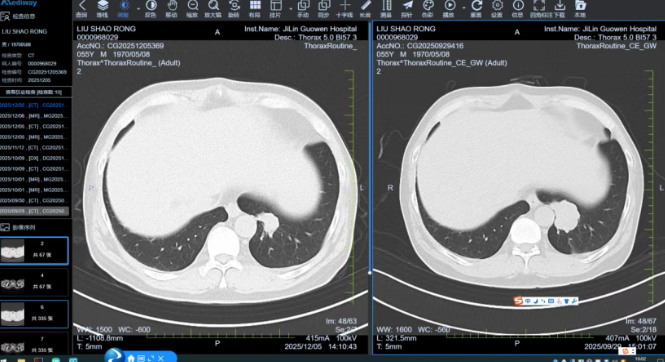

消化道肿瘤中心首席专家张晓东主任据此建议XELOX方案联合靶向药进行强化化疗,放疗科则为直肠原发灶规划精准放疗。治疗过程中,MDT团队始终保持动态跟踪。每两周期治疗后,影像科精确测量病灶变化,肿瘤内科根据反应调整方案。4周期后,评估结果令人振奋:肺部转移灶缩小,直肠原发灶明显退缩,转化治疗成功。